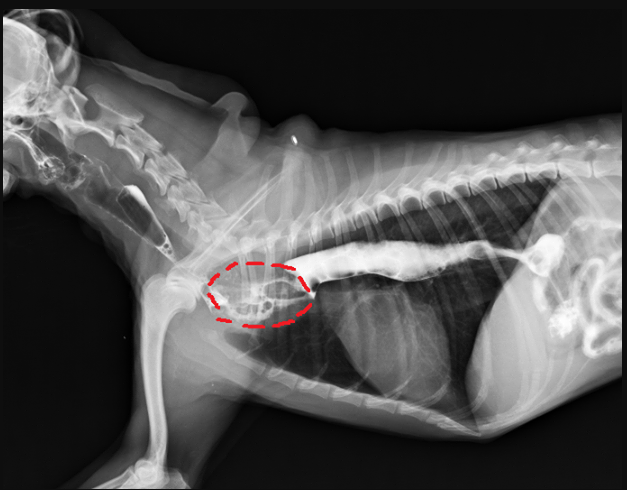

使用造影劑輔助確認下,確認異常影像位於食道,推測是大口吞入的肉塊,造成食道異物阻塞(圖二)

圖二